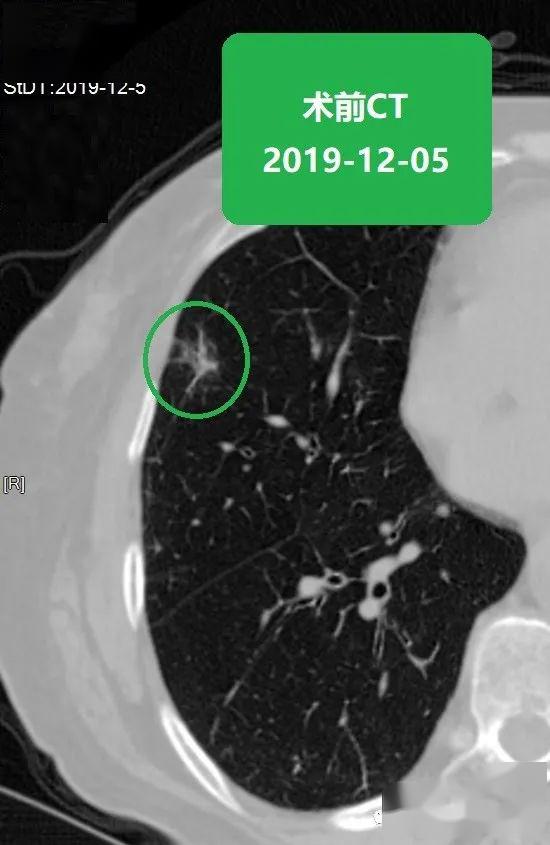

苏大附二院靳勇医生团队病例分享第47期肺磨玻璃结节的消融

图片尺寸550x845